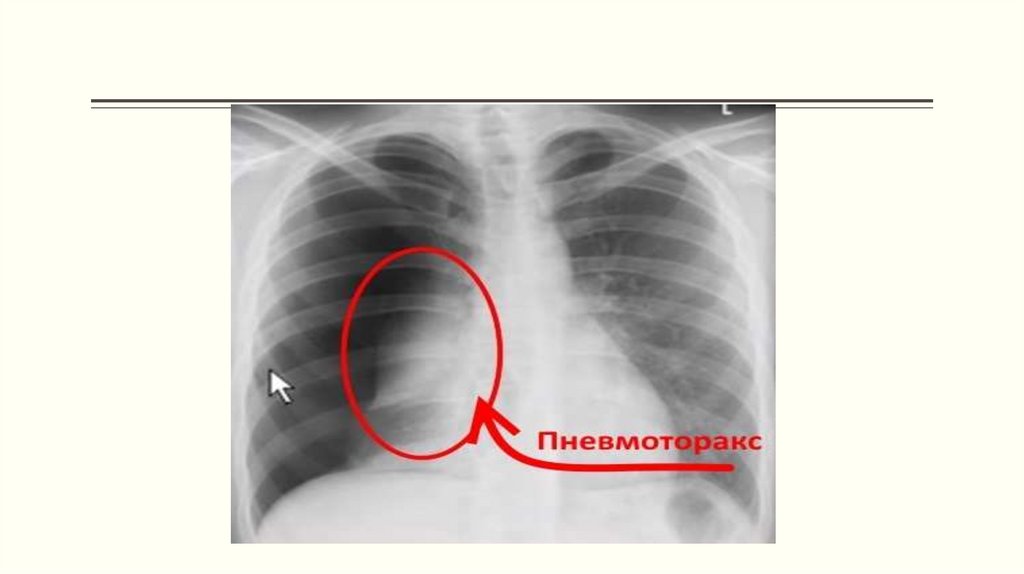

Закрытый пневмоторакс

Клапанный пневмоторакс

Гемоторакс

Открытые повреждения грудной клетки, ранения сердца и перикарда

Первая медицинская помощь при возникновении травм груди

Ушиб грудной клетки

Переломы ребер